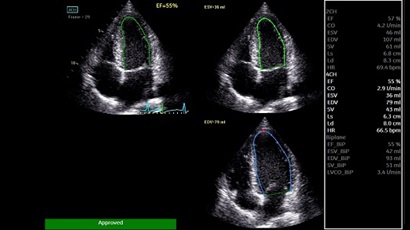

• AUTO 2D EF - режим автоматической недопплеровской количественной оценки глобальной сократительной функции ЛЖ (по Simpson).

• AFI - режим цифровой недопплеровской качественной и количественной оценки региональной сократительной функции ЛЖ.